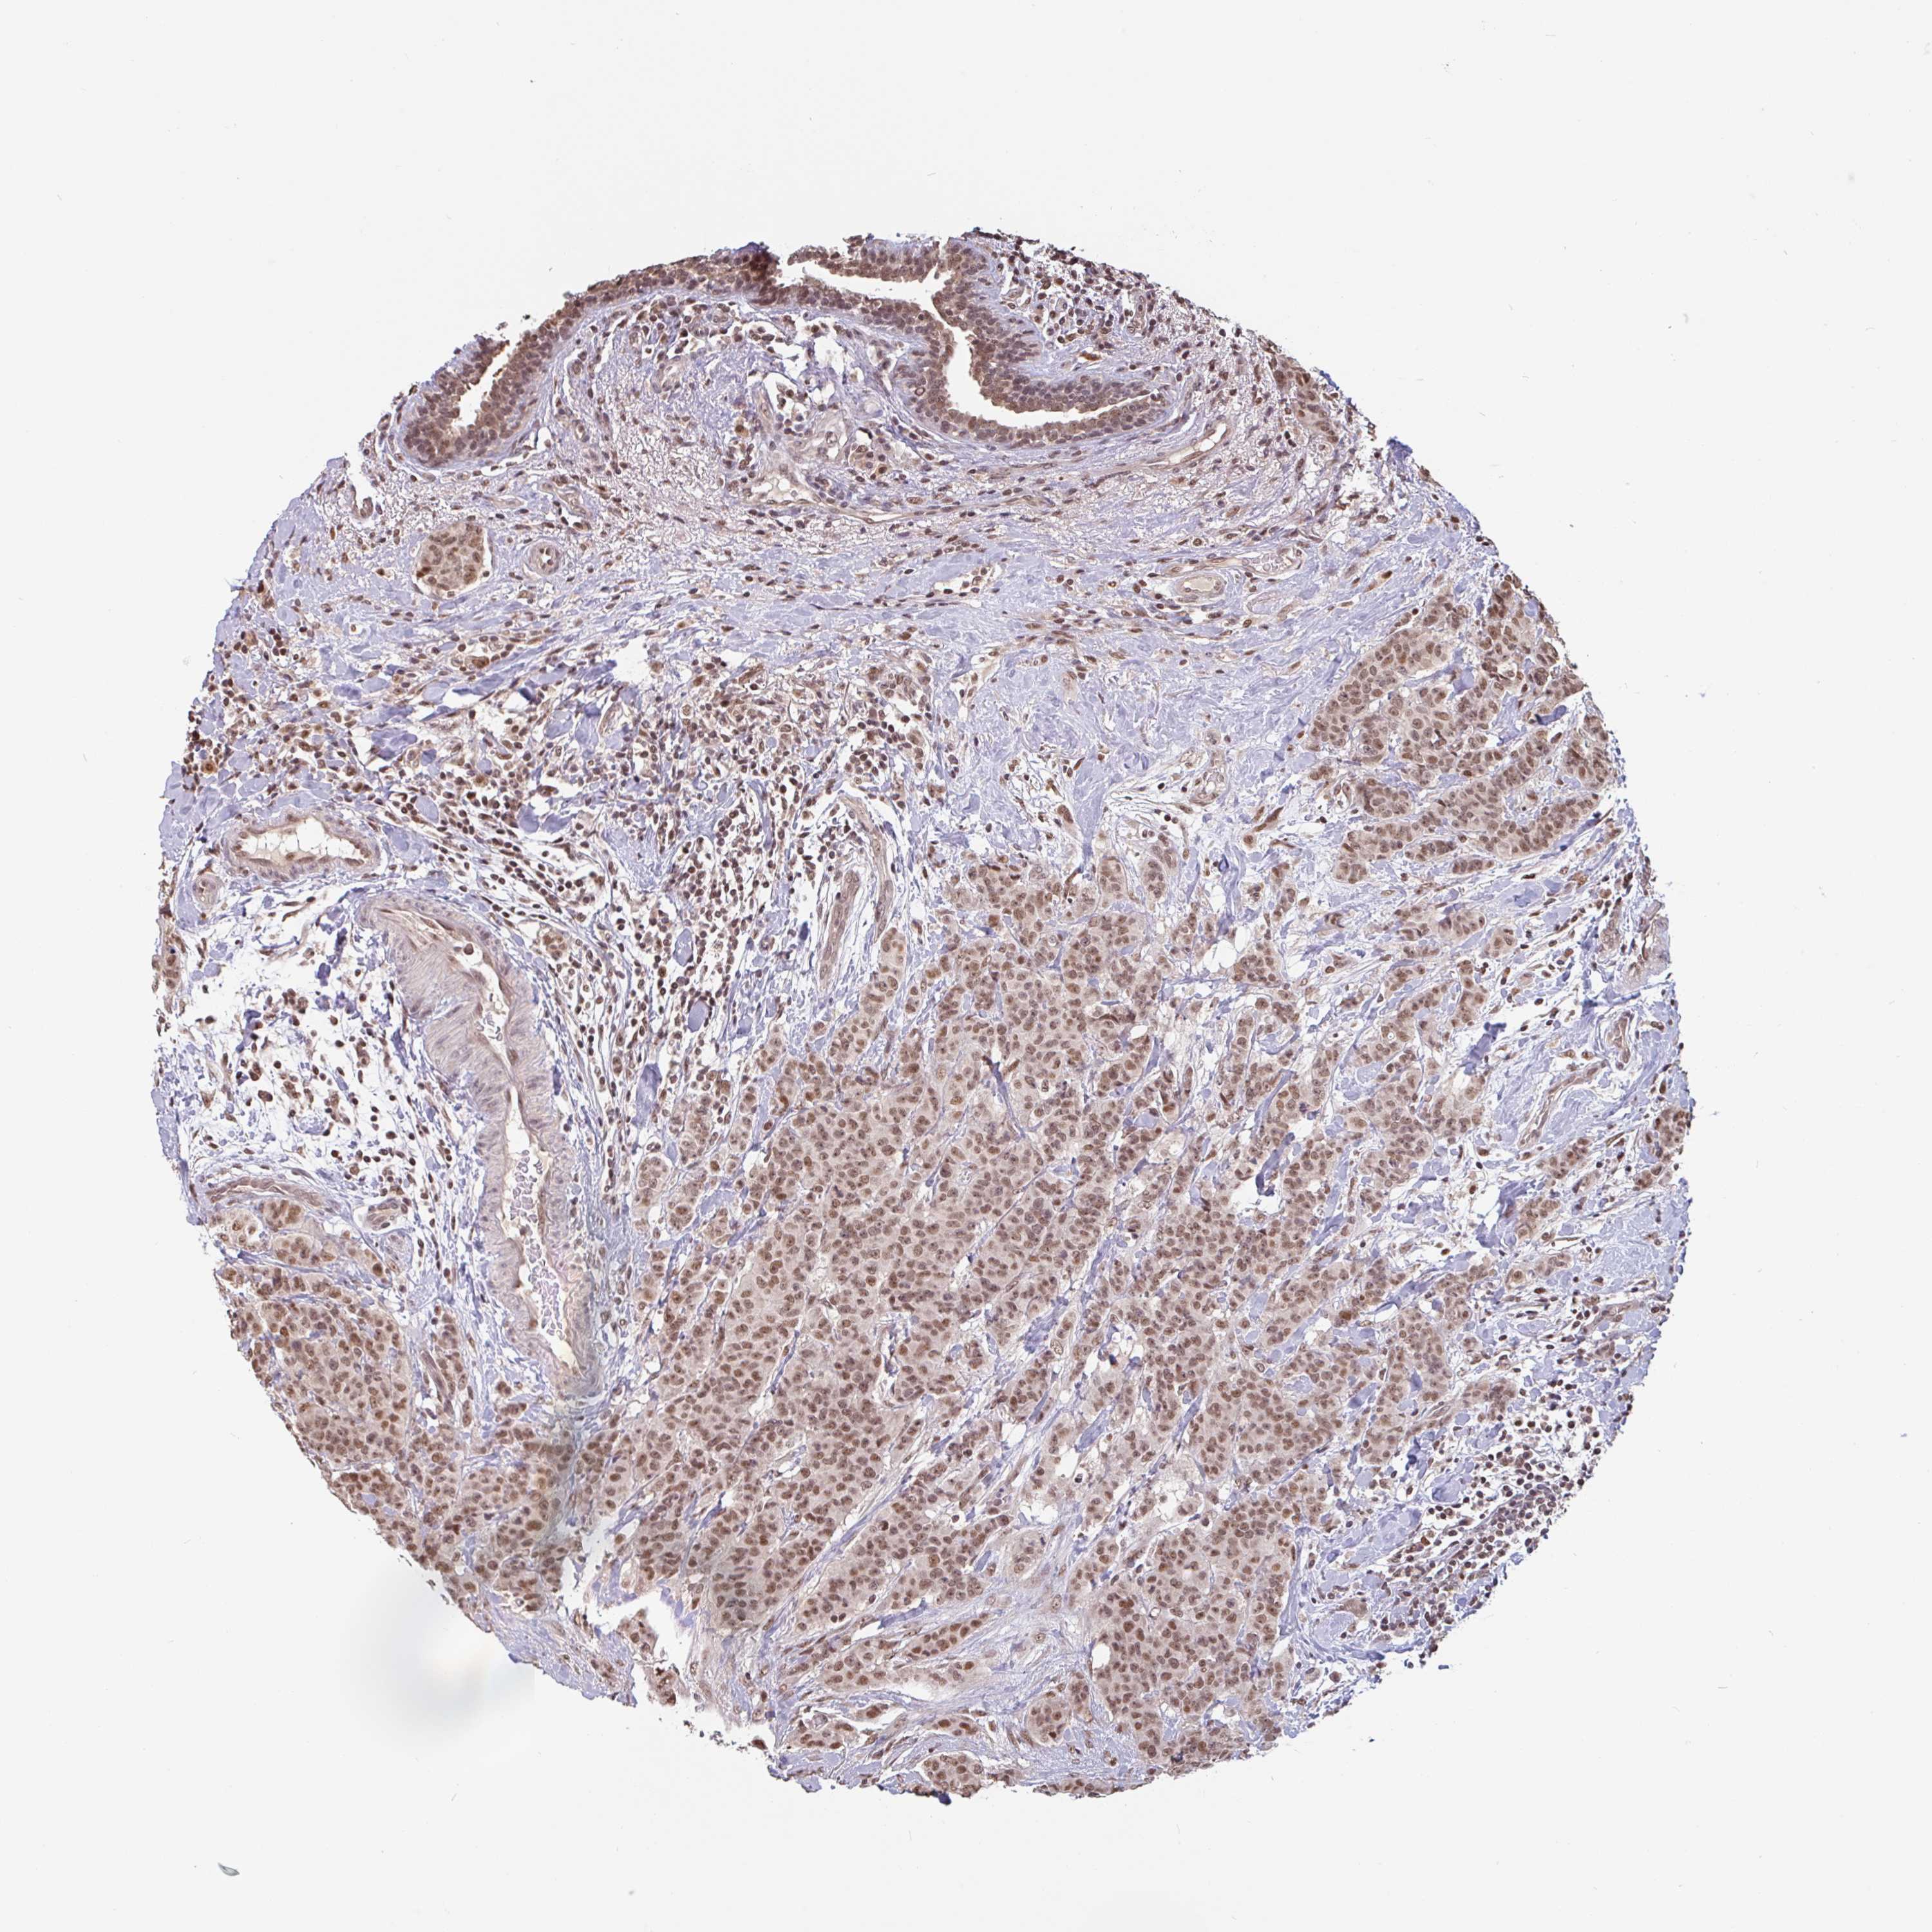

BRCA TCGA BRCA VALIDATION PROTEIN EXPRESSION

ANTIBODIES

AND

VALIDATION